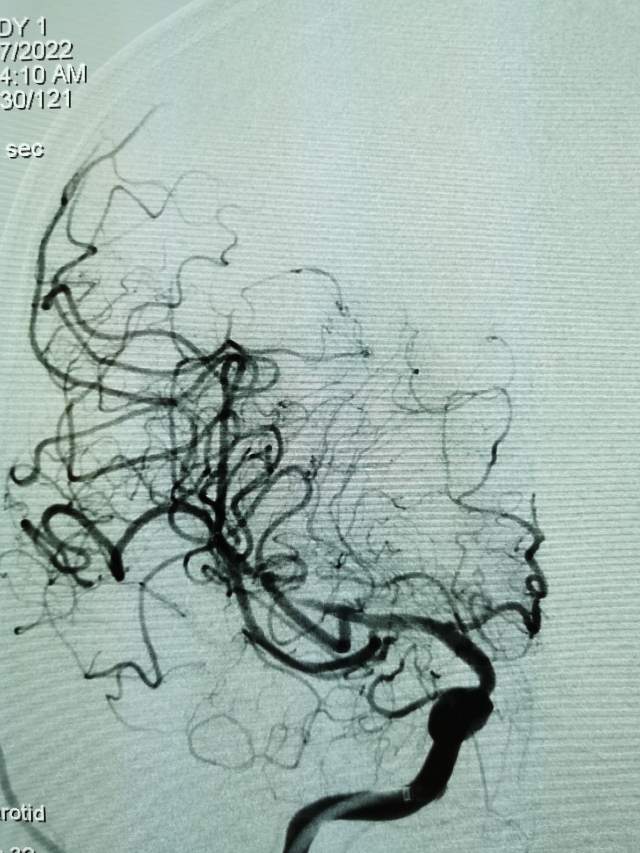

河南信阳帅哥,一个半月前突然出现左侧肢体肌力乏力、认知功能大幅下降、反应迟钝,在当地多家医院按照“脑梗塞”诊治后,症状未能缓解,仍呈进行性加重。经推荐转至我院寻求治疗,术前谈话之后,疫情期间,家里有急事需要处理,唯一的陪人回家了……。今日为患者手术,术中发现右侧大脑中动脉的一个分支出现多节段、长节段的夹层,血流仅剩断断续续的一条线,在血中飘摇,随时存在血管完全闭塞,脑梗塞继续加重,重者可能危及患者生命……,术中正确辨别真腔(误判后果严重),顺利打通重建血管,血流恢复……,手术只是整个治疗过程的一小部分,围手术期仍需要再接再励,帮助患者渡过风险期~~~

最后答案:血管夹层是导致青壮年自发性脑梗塞的罪魁祸首